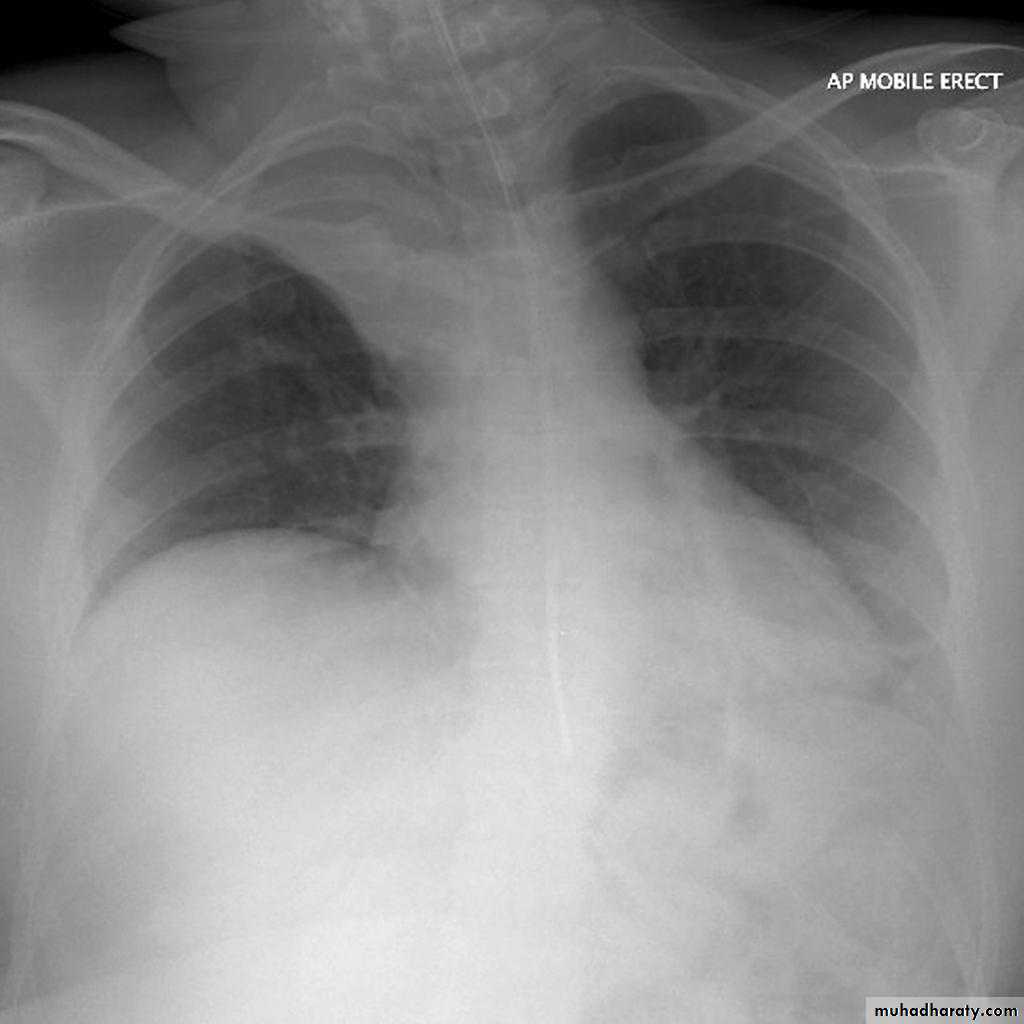

Left lower lobe collapse has distinctive features, and can be readily identified on frontal chest radiographs, provided attention is paid to the normal cardiomediastinal contours. The shadow cast by the heart does however make it harder to see than the right lower lobe collapse

Left lower lobe collapse

is readily identified in a well penetrated film of a patient with normal sized heart, but can be challenging in the typical patient with collapse, namely unwell patients, with portable (AP) often under-penetrated films, often with concomitant cardiomegaly. Features to be observed include :

triangular opacity in the posteromedial aspect of the left lung

edge of collapsed lung may create a 'double cardiac contour'

left hilum will be depressed

loss of the normal left hemidaphgragmatic outline

loss of the outline of the descending aorta

Non-specific signs indicating left sided atelectasis are usually also be present including:

elevation of the hemidiaphragm

crowding of the left sided ribs

shift of the mediastinum to the left

On lateral projection the left hemidiaphragmatic outline is lost posteriorly and the lower thoracic vertebrae appear denser than normal (they are usually more radiolucent than the upper vertebrae) .